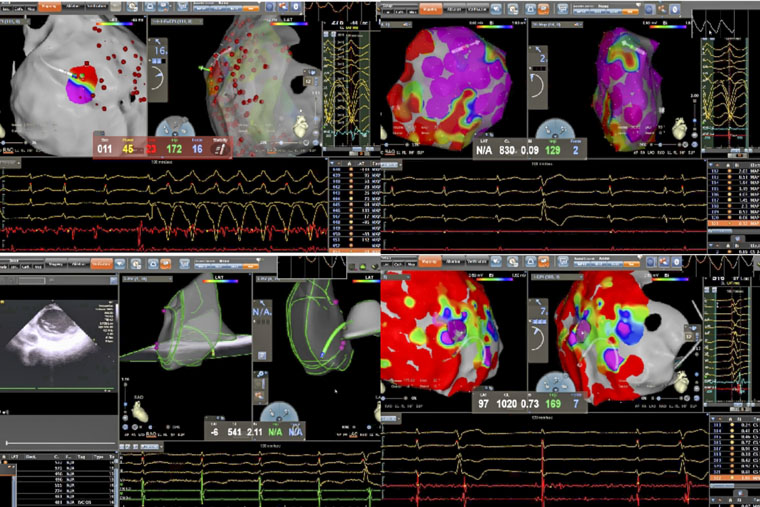

病理性室速通常指由器質性心臟病(如心肌梗死、心肌病等)所導致的室性心動過速。一名患者所患的ARVC,是一種以右心室心肌被纖維脂肪組織替代為特征的遺傳性疾病,異常的心肌結構易形成異常電傳導通路,從而引發藥物難以控制的惡性室速,傳統治療難度大、復發率高。術中,手術團隊在X線透視引導下施行心包穿刺,有效規避冠狀動脈及心肌損傷風險,為心外膜途徑消融建立安全通道。在此基礎上,同步進行心內膜及心外膜高密度標測,于右心室多部位識別出低電壓區、延遲電位等異常電活動特征,精準判定參與心動過速的關鍵區域,依托三維電生理標測系統,完成了心內膜與心外膜聯合消融。

另一名患者為61歲男性,術前發現頻發室性早搏(24小時超過10930次),部分呈三聯律及短陣室速,心電圖提示起源點為左室乳頭肌。頻發室早對即將接受大型癌癥手術的患者構成多重威脅,如麻醉可能誘發惡性心律失常、室早會影響血流動力學穩定、心臟問題還可能延誤腫瘤手術時機。心內科與胃腸外科、麻醉科迅速啟動MDT討論,一致認為必須在腫瘤手術前根除室早這一“定時炸彈”。團隊即刻啟用“電生理第三只眼”——心腔內超聲(ICE)引導手術:ICE導管送入心腔,實時顯示左室內乳頭肌形態、位置及導管貼靠情況;在ICE引導下克服乳頭肌移動難題,實現穩定貼靠與精準消融;ICE實時監測心包情況,極大避免并發癥的發生。術后患者室早完全消失,心臟風險解除,并于次日順利接受賁門癌根治術,現已康復出院。